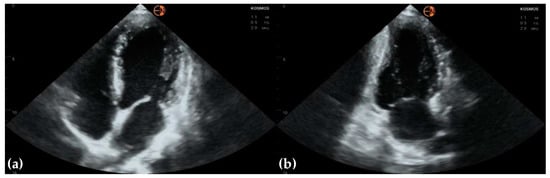

3.2. Measurements of Cardiovascular Structures

3.3. Valvular Stenosis and Regurgitation